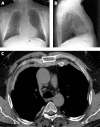

Two case histories are described of pleural and anterior mediastinal fibrosis presenting as a continuous fibrotic process with thick parietal pleural plaques extending from one pleura to the contralateral pleura through the retrosternal area, and with retroperitoneal fibrosis. Follow-up over 4 years in one case demonstrated rapid progression of disease, with pleural fibrosis preceding retrosternal and retroperitoneal fibrosis. Histopathological analysis in both cases showed non-tumoral fibrosis with broad fibrous bundles surrounding fibroblasts (and lymphocytes in one case). Possible causes such as infections and exposure to ergot derivatives were excluded. Both patients had been slightly or moderately exposed to asbestos.